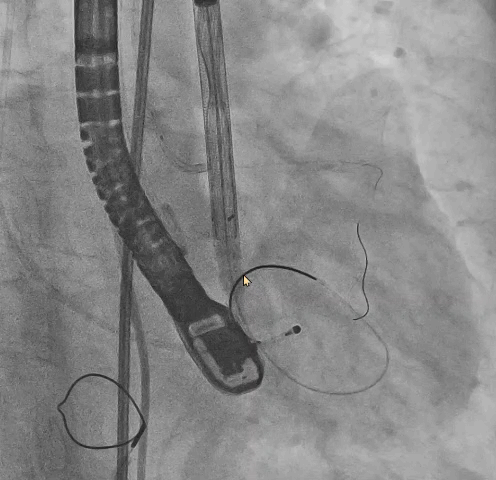

● 更换新瓣膜跨瓣后,猪尾难以送至无冠窦底,故行造影定位窦底。

隐约可见“无冠窦”后部更深窦底,位于“无冠窦”下约6mm,参考该位置后进行0位定位,无起搏逐步释放至工作位,瓣膜无明显位移表现,瓣膜形态压缩良好,造影评估无反流。准备释放瓣膜。

无张力释放,脱钩后瓣膜略微下滑,约位移瓣环下4~5mm位置,瓣膜整体形态良好,造影评估无可见反流。

超声评估,微量瓣周反流,二尖瓣工作良好,植入位置理想。